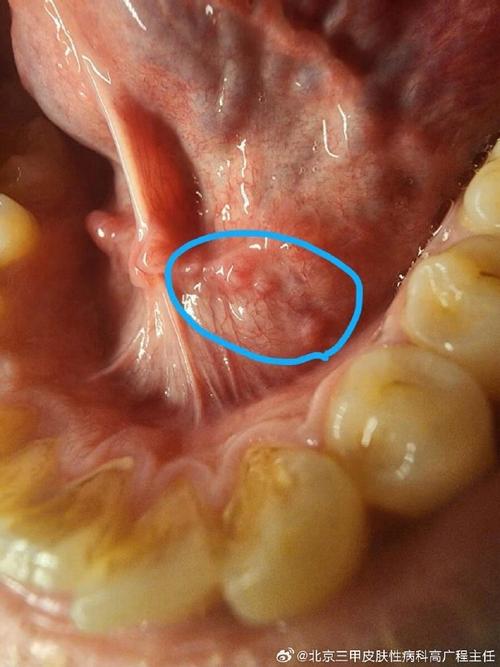

下面我为您分析一下口腔上颚长硬疙瘩的几种常见可能性,您可以根据自己的情况进行初步判断,但最终还是要以医生的诊断为准。

口腔癌(如鳞状细胞癌)

这是最需要警惕,但相对少见的情况。

- 外观:

- 通常表现为长期不愈合的溃疡(超过两周)。

- 肿块质地坚硬,像骨头一样,且固定不动(与周围组织粘连)。

- 表面可能凹凸不平、呈菜花状。

- 早期可能没有疼痛感,但后期可能出现疼痛、麻木、出血、张口受限等症状。

- 高危因素:长期吸烟、酗酒、咀嚼槟榔、HPV病毒感染等。